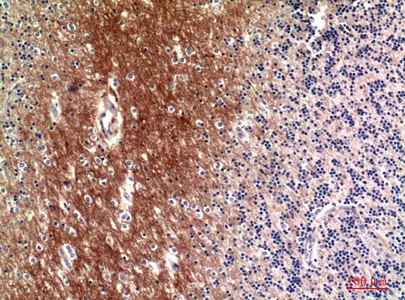

C4A/B Rabbit Polyclonal Antibody

Cat: APRab00500

Size1:50μl Price1:$150

Size2:100μl Price2:$280

Size3:500μl Price3:$1200

Size2:100μl Price2:$280

Size3:500μl Price3:$1200